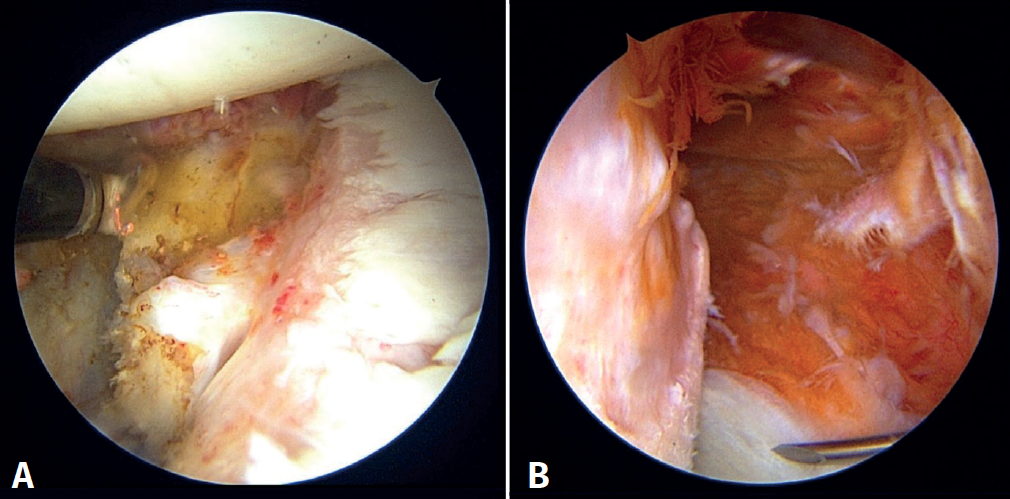

The patient is repositioned in lateral decubitus. Before placing the fields, a physical examination is performed to check glenohumeral instability with the modified anterior and posterior drawer tests(15). The humeral head is shown to engage in the glenoid with the arm in abduction and external rotation(6)(Video 1). Longitudinal traction is applied to the limb to be operated upon, according to the standard arthroscopy procedure. Arthroscopy is started through the posterior portal. An initial assessment of the location and extent of the lesions is made (Figure 2); the anterior portal is established under direct vision with the aid of a needle, 1-2 cm inferomedial to the anterolateral corner of the acromion, to penetrate within the rotator interval. An anterosuperior portal and a posteroinferior auxiliary portal are also established using an outside-in technique 2-3 cm below the posterior portal(16).

First, the glenoid is debrided with the aid of a shaver-type motor, and free bodies and bony debris are removed. The labrum and capsule are detached together from the glenoid margin, creating a wide recess to accommodate the graft, and the surface is prepared by creating bleeding edges with a burr. Then, using a posteroinferior auxiliary portal established under direct vision (Figure 3A), remplissage is started with debridement of the Hill-Sachs lesion and the placement of two bone implants - in this case HealicoilRegenesorb® (Smith & Nephew Inc., Andover, MA, USA) 4.5 mm double suture Ultrabraid® N.2 (Smith & Nephew Inc., Andover, MA, USA ) (Figures 3B and 3C). The 8 extremities are retrieved, passing them through the capsule approximately 1 cm apart and using a Sling-Shot® device (Stryker) (Figures 3D, 3E and 3F). The extremities are left untied in the posterior portal.